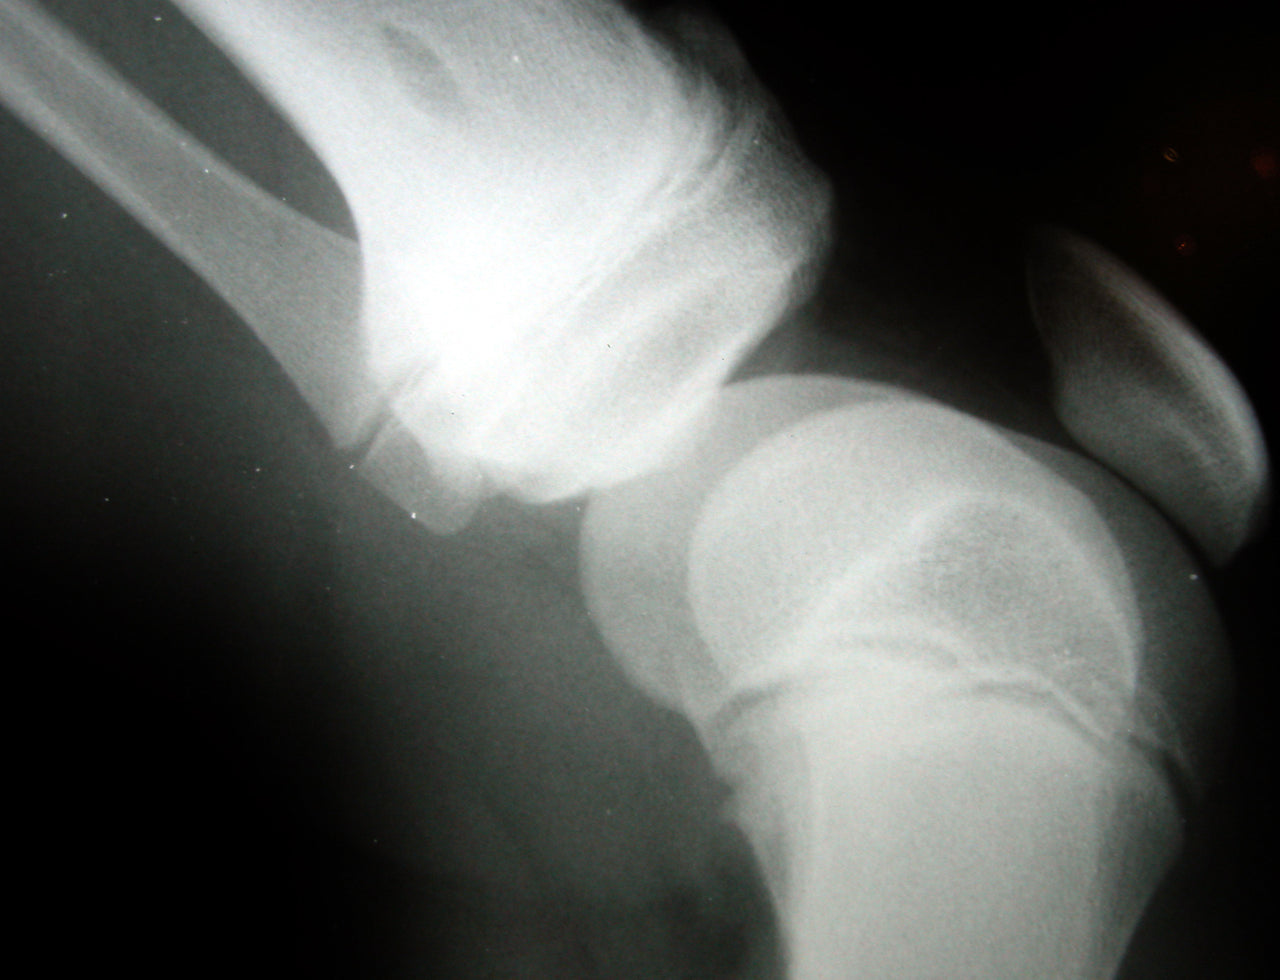

Osteoartritis: una enfermedad muy común

La artritis es un conjunto de afecciones diferentes que tienen en común que causan inflamación articular, hinchazón, rigidez y dolor que conducen a una pérdida de la función articular. La prevalencia de la artritis de rodilla aumenta con el envejecimiento de la población y se ve agravada por el creciente número de personas obesas y de edad avanzada. Varios estudios realizados en los últimos años han sugerido que la deficiencia de vitamina D en adultos puede agravar la osteopenia, la osteoporosis, la debilidad muscular, las fracturas, las enfermedades autoinmunes, las enfermedades infecciosas y las enfermedades cardiovasculares. Los bajos niveles de vitamina D medidos en suero como 25-hidroxivitamina D (25(OH) D) en ancianos y obesos se correlacionan con varios trastornos de salud, entre ellos el dolor crónico.